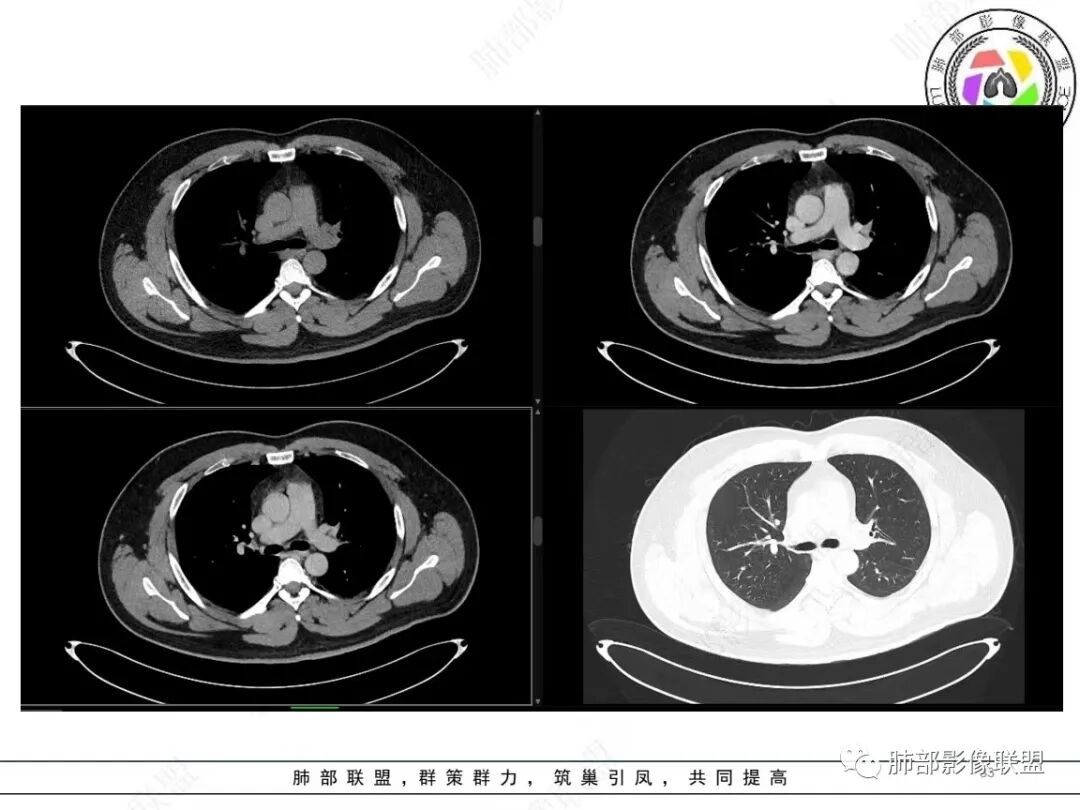

中年人,咳血,左肺上叶实性团块,边界清晰,与胸膜分界不清,可见栽赃表现,病灶推挤支气管及肺血管内移,增强可能条纹血管影,总体强化明显,考虑恶性或交界性肿瘤,间叶组织来源,肉瘤,SFT,肉瘤样癌,滑膜肉瘤。

左肺上叶胸膜肿块,浅分叶,边缘光整,密度不均匀,周围气管及血管受压推移,边缘强化,考虑肉瘤,鉴别SFT

左肺上叶占位,平扫密度较低,临近胸膜栽赃桩,外向内生长,边缘有膨隆、毛糙,增强后轻度强化,边缘弧线样强化,考虑肉瘤样癌

左上肺软组织肿块,周围散在磨玻璃影,界不清,窄基底贴于胸壁,胸膜下脂肪间隙不清,呈低强化,胸膜下见。与主病灶强化方式一样的病变,2R区见肿大淋巴。考虑恶性,间叶组织来源合并出血。

青年男性,咯血;CT示左肺上叶胸膜下软组织肿块,边界尚清,宽基底与胸膜相连,增强动脉期内见细条状血管影,轻度延迟强化,定位:肺外,胸膜外脂肪存在,考虑脏层胸膜起源;定性:考虑SFT。

影像表现:左肺上叶占位合并出血,胸膜栽赃,边缘强化,局部见血管影,中心密度20Hu,无强化,符合非液化坏死。定位:肺内,定性恶性(明显血管影,栽赃排除错构瘤,中心无强化排除PSP,无明显清楚的坏死边界,强化不符合肉芽肿,排除结核),年龄轻,无长时间吸烟史和肺气肿改变,肉瘤样癌可能性很小,与支气管无确切关系,所以病理类型考虑来源于肺间叶组织的肉瘤,骨外尤文?滑膜肉瘤?

有血供,强化不明显,周围肺出血,肺组织受压改变,定位肺外,胸膜增厚,部分胸膜下脂肪间隙存在,不确定肋骨是否受侵犯,部分层面与肺动脉分界不清,感觉推移,如果供血要考虑sft,强化不符合,有血管进入,但是强化不明显,密度相对均匀,所以不考虑坏死,富含粘液可能,咯血,说明累及支气管了,有一定侵袭性,肿块大,考虑间叶来源肿瘤,与胸膜接触面相对不是宽基底,综合考虑滑膜肉瘤可能,典型的滑膜肉瘤一般铺路石改变,这个又觉得信号相对均匀了一些学习中

定位肺内明确,来源间叶组织明确,年龄和吸烟史情况排除肉瘤样癌,剩下的就基本上只有骨外尤文和滑膜肉瘤了,再加上强化低,骨外尤文就肯定首先考虑。